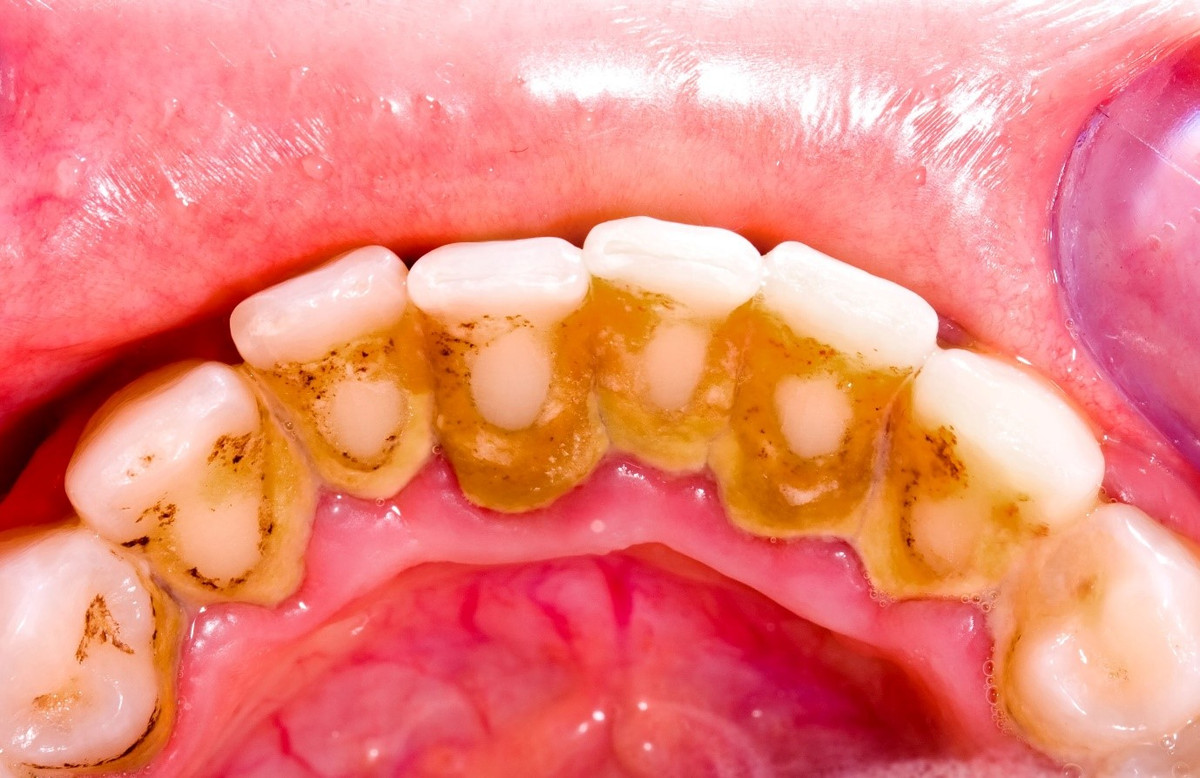

Cao răng không ngờ lại là thủ phạm gây nhiều bệnh thế này

Cao răng (hay vôi răng) do cặn vụn dư thừa của thực phẩm bám dính vào thân răng, chui xuống nướu răng. Từ đó hình thành mảng bám, theo thời gian phản ứng với những vi khuẩn, nước bọt... trong miệng lắng đọng lại, tạo thành cao răng.

Tốc độ tạo cao răng ở mỗi người một khác, sự hình thành của nó bị ảnh hưởng của những thành phần có trong nước bọt, thói quen ăn uống, thói quen vệ sinh răng miệng.

Nguyên nhân dẫn đến cao răng là do thói quen vệ sinh răng miệng: Không chải răng thường xuyên, không dùng chỉ nha khoa, không lấy cao răng định kỳ 6 tháng/lần; ăn nhiều thức ăn ngọt (bánh kẹo, đồ uống có đường sẽ khiến các mảng bám hình thành nhanh hơn, tạo điều kiện thuận lợi cho vi khuẩn hoạt động gây nhiều bệnh tật về răng miệng). Những người hút thuốc lá, nghiện trà, cà phê,... cũng là nhóm đối tượng chịu sự tấn công của vôi răng - mảng bám nhiều bất thường.

Tác hại của cao răng

Mảng bám cao răng chứa 400 loài vi khuẩn khác nhau và hàng tỷ vi trùng sinh sôi trong mỗi mg mảng bám. Hầu hết các vi trùng có hại và chúng có thể gây tổn hại cho răng, nướu răng khi nó tập trung thành lớp dày. Chính vì thế, cao răng là một trong những nguyên nhân gây bệnh ở lợi và quanh răng. Cao răng có thể dẫn đến các bệnh như viêm lợi, với các biểu hiện đánh răng chảy máu, miệng có mùi hôi. Cao răng cũng có thể gây viêm nha chu dẫn đến tiêu xương làm răng bị đau, ê buốt khi ăn uống, nặng hơn có thể gây lung lay và rụng răng. Cao răng còn gây ra viêm tủy ngược dòng. Ngoài ra, khi miệng chứa nhiều vi khuẩn từ cao răng, khi nhai và nuốt thức ăn, vi khuẩn sẽ theo thức ăn đi vào đường ruột và xâm nhập cơ thể từ đường tiêu hóa.

Cao răng là một trong những nguyên nhân gây bệnh ở lợi và quanh răng.